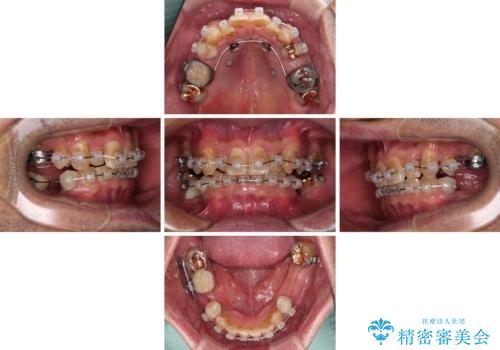

- 下顎両側の欠損と上顎前歯のデコボコを気にして来院された患者様です。

デコボコは今まで気にせずにいたそうですが、奥歯の欠損改善を機に、矯正治療に興味があるので、相談したいとのことでした。

奥歯に欠損が多く、矯正治療はやや難航することが予想されますが、患者様の希望もあり、上顎左右小臼歯を1本ずつ抜歯し、ワイヤー装置にて矯正治療を行うこととしました。

矯正歯科治療を行うに当たり、痛みや違和感を感じている歯の根管治療を行い、矯正治療中にインプラント埋入し、補綴治療と矯正治療を同時に終了できるように進めて行くこととしました。